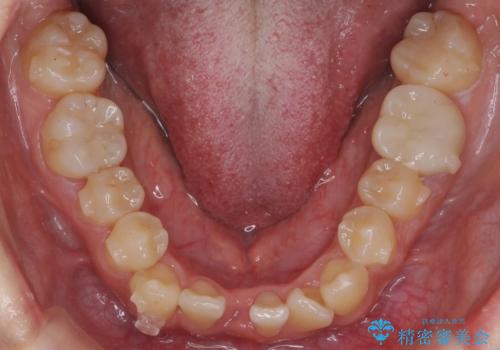

- 八重歯を治したいと来院。

古典的な治し方ですと上下左右4本抜歯してワイヤー矯正です。

今回は口元も出ていないうえに、右上のみの八重歯のため奥歯を後ろに下げて治療しました。

ただし、下の前歯は入りきらない為1本のみ抜歯しています。